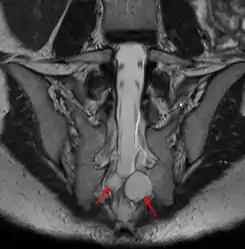

Los quistes de Tarlov (QT), también denominados quistes perineurales, periradiculares o quistes aracnoideos extradurales, son pequeñas masas que se forman a expensas de las dos capas más internas de las meninges, la piamadre y el aracnoides. Los quistes, que contienen líquido cefalorraquídeo (LCR), presentan un pedículo, a través del cual se comunican con el espacio subaracnoideo espinal, y se sitúan alrededor de los nervios de la zona sacra y lumbar, y suelen diagnosticarse de manera incidental en el transcurso de una Resonancia Magnética (RMN). Por lo tanto, si bien los QTs son quistes perinerviosos, corresponden a una dilatación de la dura madre y son pues una enfermedad de la dura madre y no de las raíces nerviosas, que son afectadas de forma secundaria (compresión) por estos quistes.

En cuanto a su ubicación, los QT’s se encuentran habitualmente en la zona sacra alrededor de las raíces nerviosas posteriores, los quistes anteriores son escasos. Los QT’s múltiples no son raros. Aunque un quiste de gran tamaño puede causar síntomas por presión de una estructura o nervio adyacente, los síntomas pueden también ser causados por la presión que ejerce el LCR en los nervios situados en el interior del quiste o en su pared (4). Por lo tanto quistes menores incluso de 1 cm pueden ser altamente sintomáticos.